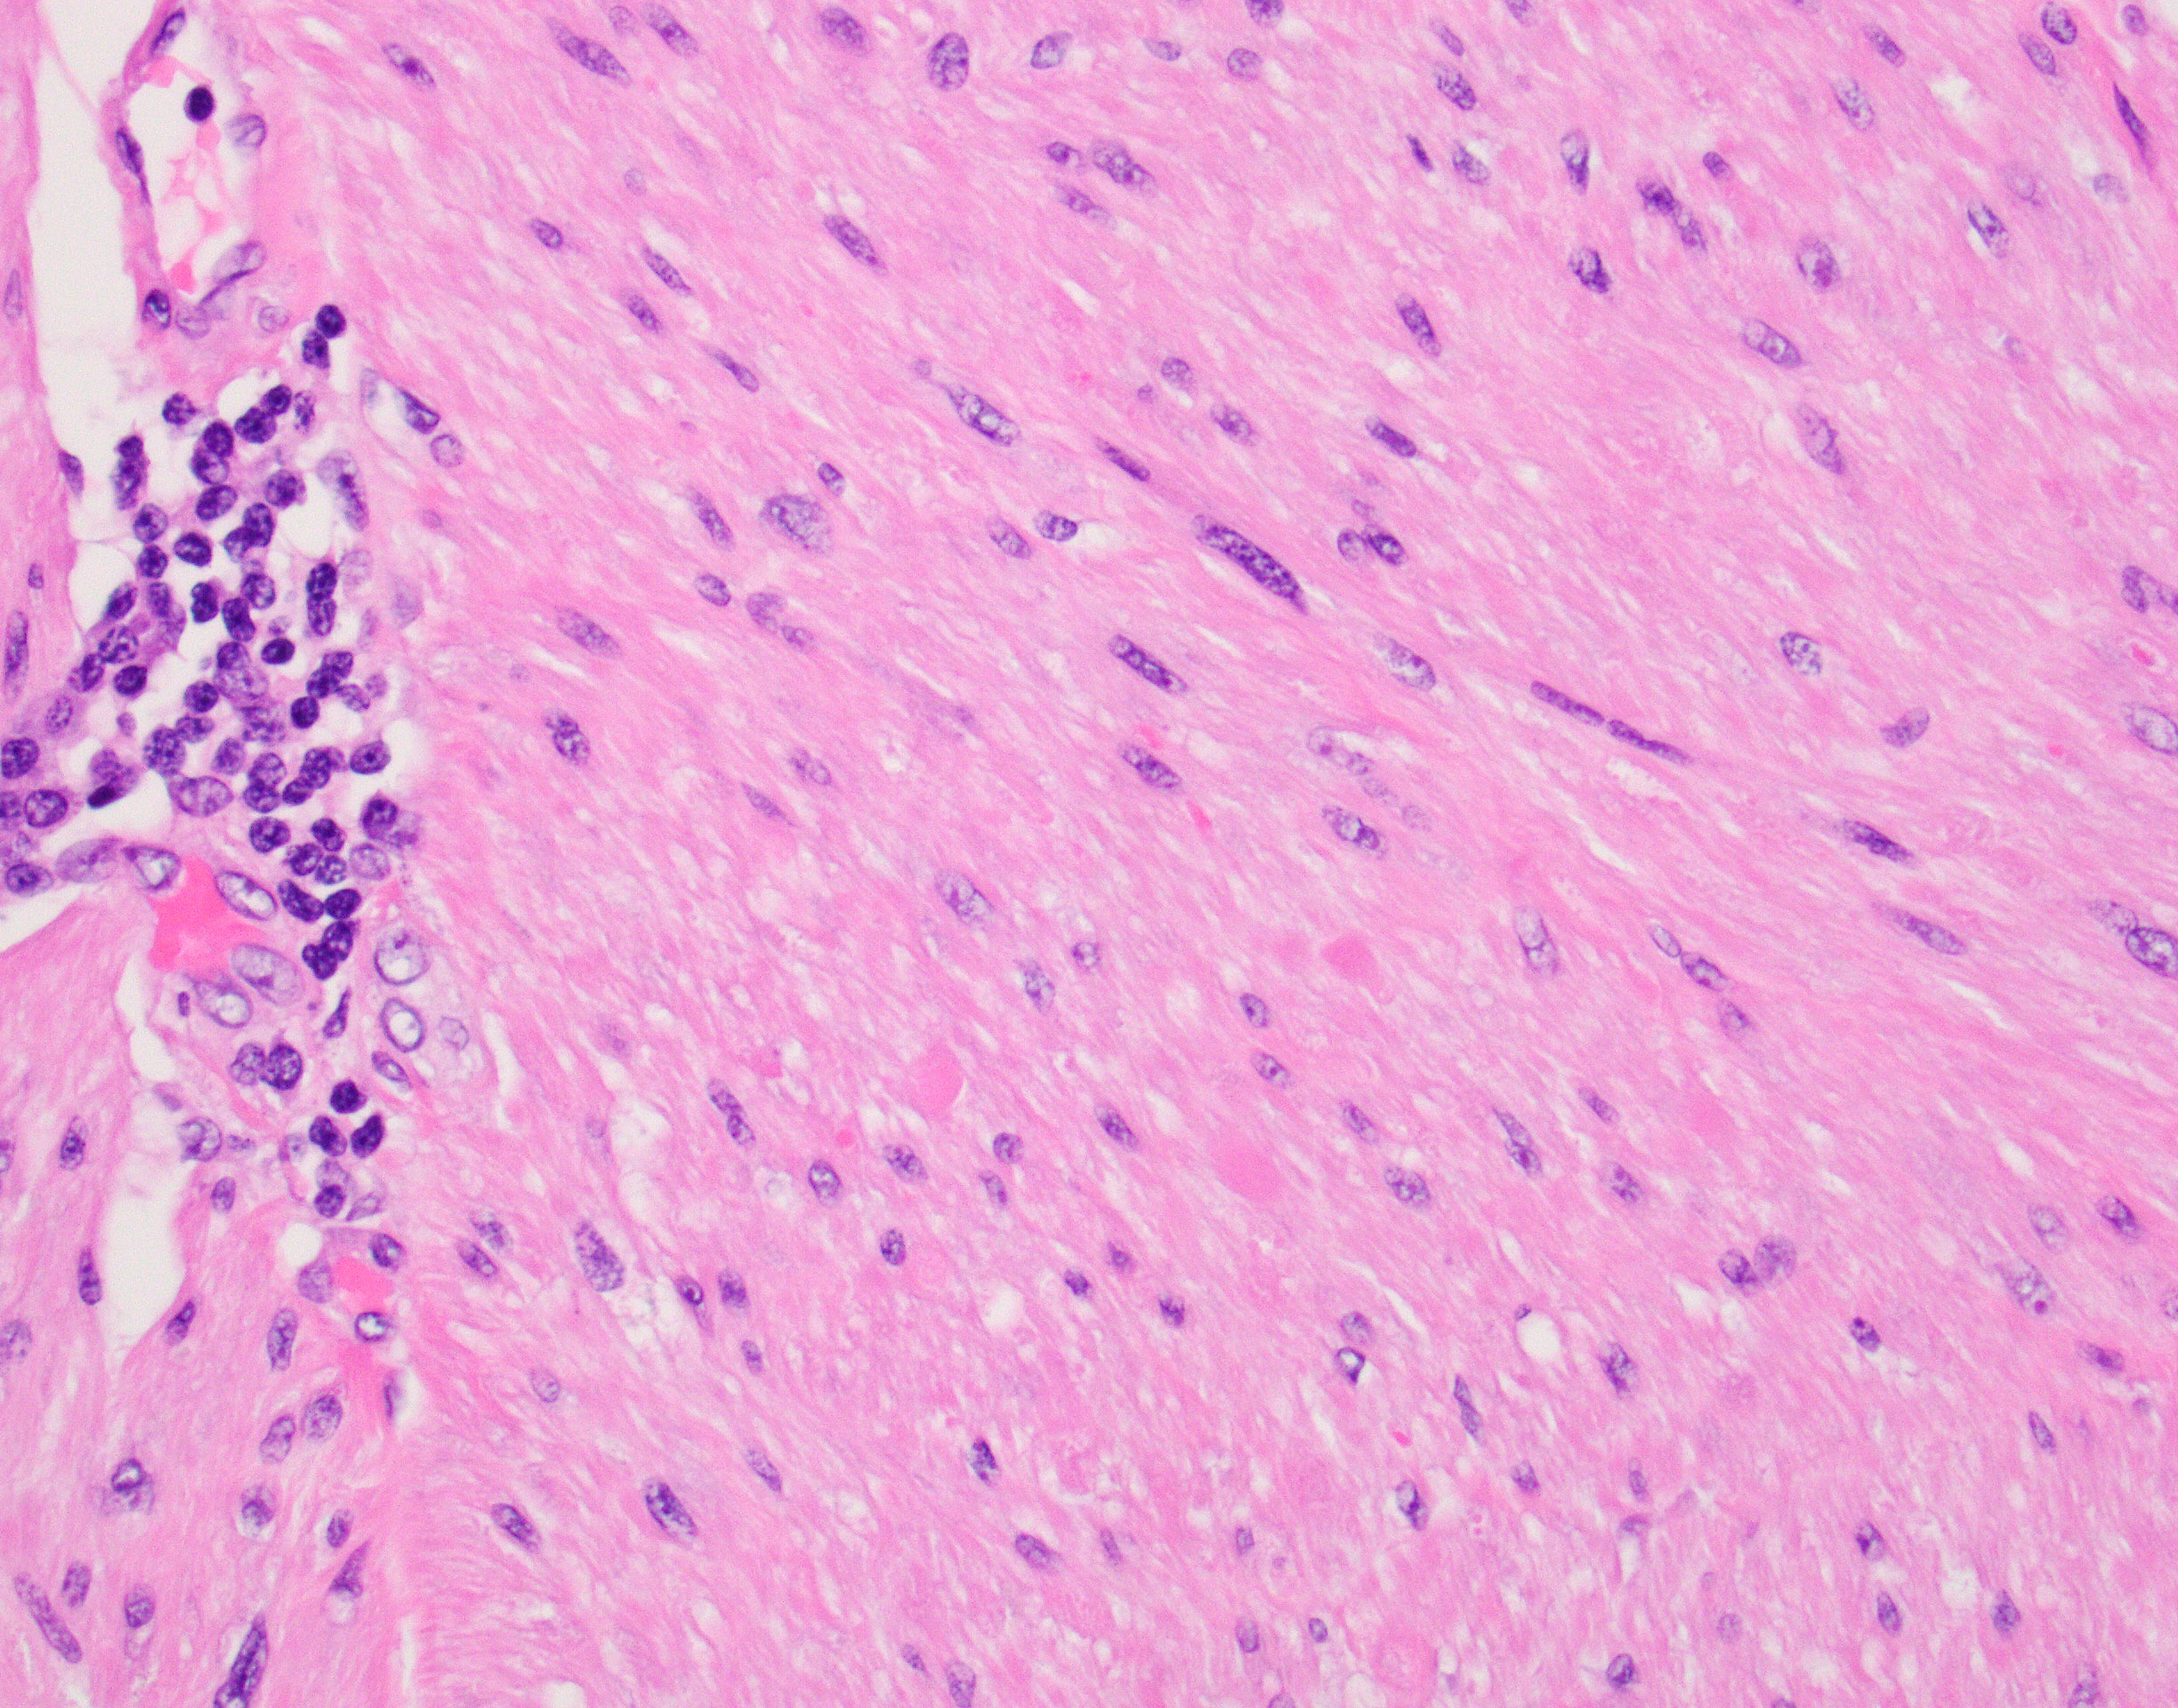

The patient is showing well-circumscribed (Fig 1) leiomyomatous lesions with features of the Hereditary Leiomyomatosis and Renal Cell Cancer (HLRCC) Syndrome (OMIM 150800, AKA Reed’s syndrome) which is produced due to germline mutations of the gene coding for the mitochondrial enzyme Fumarate Hydratase (FH, 1q43). This syndrome is characterized by multiple cutaneous, and in women uterine, leiomyomas exhibiting some distinctive features seen in this particular lesion; mainly cytoplasmic eosinophilic globules (Figure 2), nuclei with powdery chromatin exhibiting prominent nucleoli (Figure 3). Uterine examples tend to show similar albeit more pronounced nuclear features in addition to Hemangiopericytoma-like (HPC-like) vasculature, nuclear periodicity among other unique characteristics. Likewise, renal cell carcinomas arising in the context of HLRCC have their own set of distinct features including similar powdery chromatin and large nuclei with viral-like macronucleoli. These renal tumors were historically classified as type II papillary renal cell carcinomas (RCCs) or unclassifiable RCCs. The absence of the normal enzyme can be demonstrated by immunohistochemistry for Fumarate Hydratase (FH), which will show loss of staining in the lesional cells like in our case (Fig 4). In addition, one could performed immunohistochemistry for the abnormal product of the mutated FH gene (2-Succinocysteine, 2SC) a test that is not widely available.